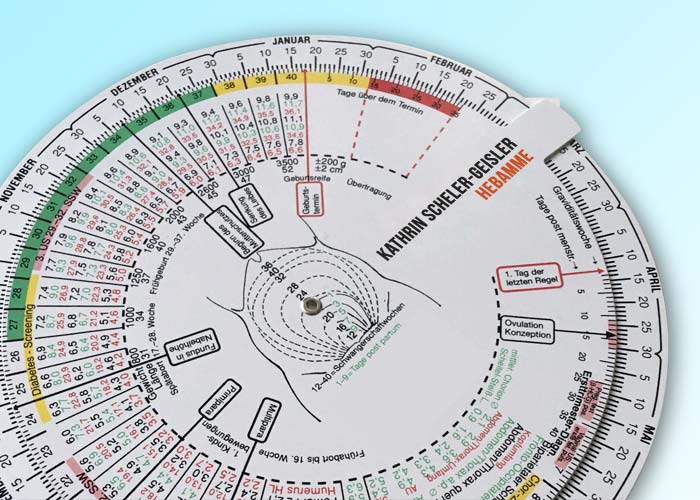

- Vorsorgeuntersuchungen (auf Grundlage der Mutterschaftsrichtlinien)